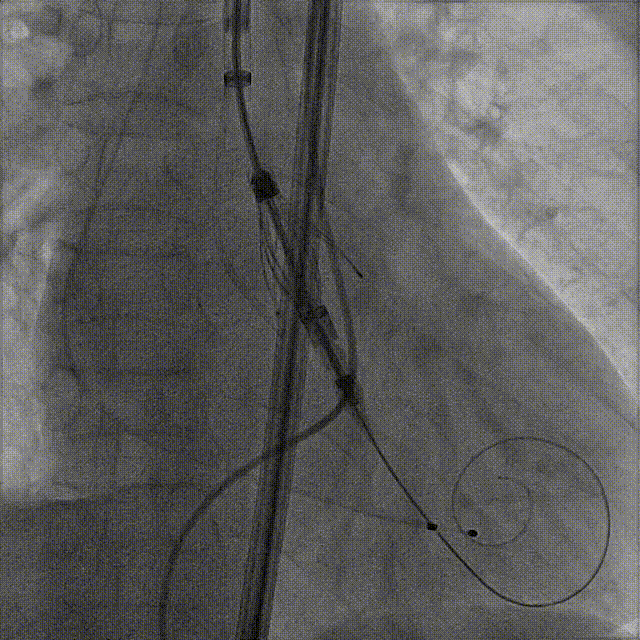

Case 2

大瓣环合并瓦氏窦、心室扩张,外周小弓角

术前CT评估

根据瓣环与 LVOT-6 mm 平面,选择:M 号 TaurusTrio,瓣环可提供7.3%oversize

手术过程:5A 标准化流程SOP

右窦中心造影

大鞘到STJ

瓣膜调弯后解离

瓣膜右窦中心调整

定位键窦不对齐

灵活旋转操作

确认窦对齐

入窦

无窦超选验证

左窦超选验证

一键释放

术后造影